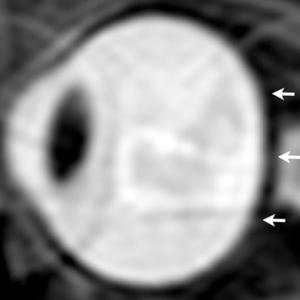

The results showed that, compared to short-duration astronauts, long-duration astronauts had significantly increased post-flight flattening of their eyeballs and increased optic nerve protrusion. Long-duration astronauts also had significantly greater post-flight increases in orbital CSF volume, or the CSF around the optic nerves within the bony cavity of the skull that holds the eye, and ventricular CSF volume—volume in the cavities of the brain where CSF is produced. The large post-spaceflight ocular changes observed in ISS crew members were associated with greater increases in intraorbital and intracranial CSF volume.

"If the ocular structural deformations are not identified early, astronauts could suffer irreversible damage," he noted. "As the eye globe becomes more flattened, the astronauts become hyperopic, or far-sighted."